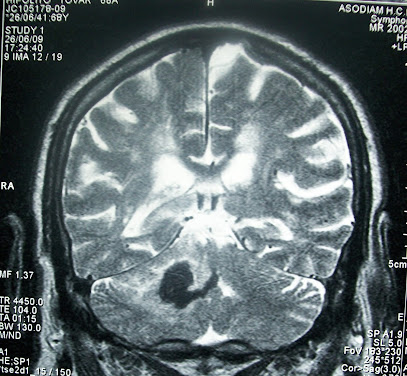

Accidente cerebrovascular (ACV)

- Un accidente cerebrovascular (ACV) ocurre cuando el suministro de sangre a una parte del cerebro se interrumpe o se reduce, lo que impide que el tejido cerebral reciba oxígeno y nutrientes.

Existen dos causas principales de ACV: una arteria bloqueada (ACV isquémico) o filtración o ruptura de un vaso sanguíneo (ACV hemorrágico). Algunas personas pueden tener sólo una interrupción temporal del flujo sanguíneo al cerebro, conocida como un ataque isquémico transitorio (AIT), que no causa síntomas duraderos.

2. ACV hemorrágico

Ocurre cuando un vaso sanguíneo en el cerebro gotea o se rompe. Las hemorragias cerebrales pueden ser el resultado de muchas afecciones que afectan los vasos sanguíneos. Los factores relacionados con el ACV hemorrágico incluyen lo siguiente: